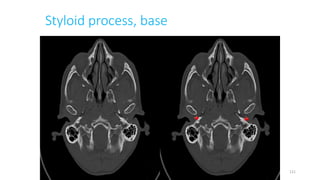

Styloid process, base